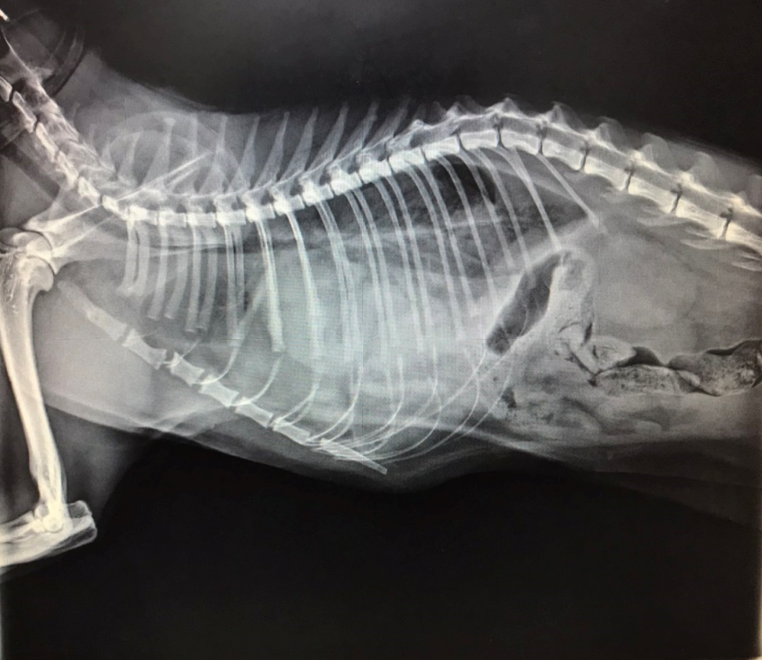

X光下,橫膈分界消失,左側胸腔有不正常軟組織影像

手術後X光,胸腔內異常軟組織影像已經消失

橫膈的邊緣又出現,胸腹腔有完整分界